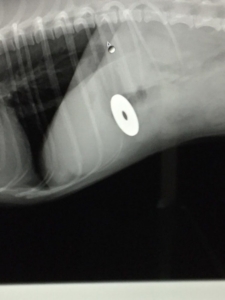

レントゲンを撮ると胃の中に何かある・・・。

レントゲンで映るもの、映らないもの

何か食べられたかもという時に真っ先に行う検査はレントゲンです。

ただしレントゲンは胃の中の内容物をはっきりと映し出すことはあまりありません。

硬いもの、金属製のものであればはっきり映るのですが、ゴム製のおもちゃや鳥の骨などは角度によってははっきり映りません。